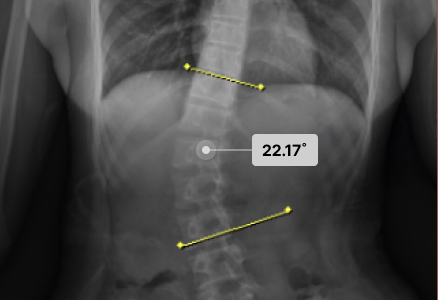

척추측만으로 휘어진 허리 때문에 일상조차 버거웠던 환자분들이

두드림의 교정치료를 통해 뚜렷한 변화와 회복을 경험하고 있습니다.

· 각 치료사례는 환자분들에게 사전 동의를 받아 동일 조건에서 촬영된 이미지입니다.

· 개인에 따라 치료 결과가 달라질 수 있으니 의료진과 충분한 상담 후 치료를 진행하시길 권장드립니다.